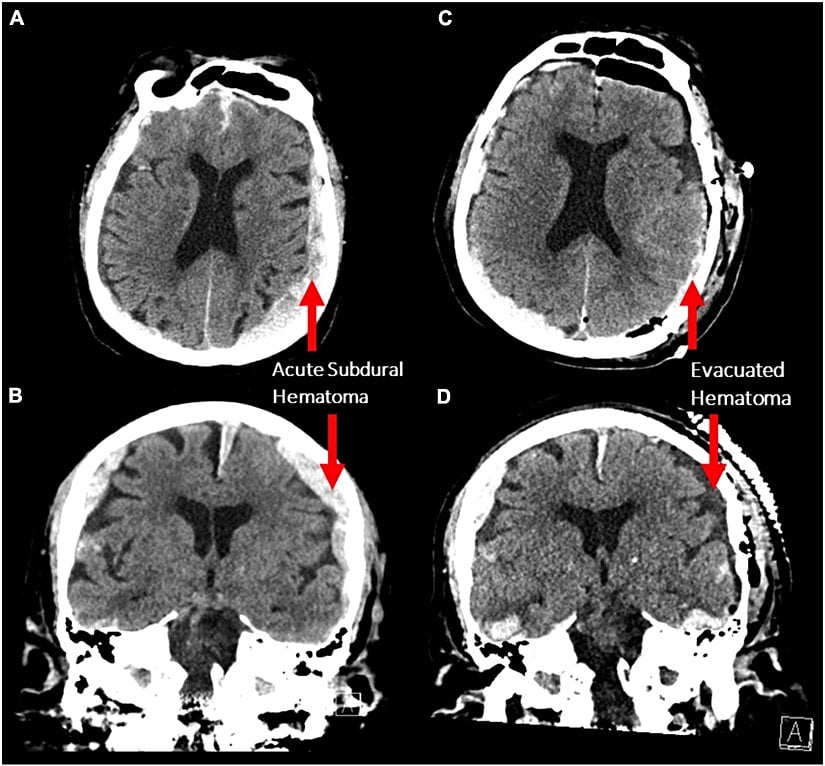

Dr. Vicente ve ekibi de 87 yaşındaki hastalarının bu şekilde EEG kaydını alıyorlardı. Hasta (yaşlılarda ne yazık ki çok yaygın bir problem olduğu üzere), düşüp kafasını vurmuştu. Yapılan tomografi sonucunda beynin iki tarafında da subdural, yani beyni saran sert zarın altında kalan hematom, yani kan yumrusu görüldü:

Hemen ameliyata alınan hastanın sol taraftaki daha şiddetli hematomu boşaltıldı ve hastanın durumu bu sayede 2 gün boyunca sabitlenebildi; ancak hasta yoğun bakımdayken bacaklarında kasılmalar ve epileptik nöbetler başladı. Bu nedenle nörolojiye danışan doktorlar, EEG çekilmesine karar verdiler. Kalp krizi ve ölümü de içeren EEG kayıtları şu şekildeydi: